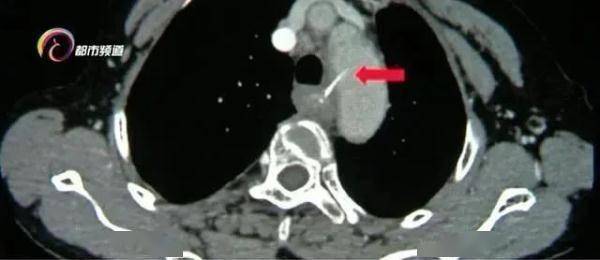

疼痛难忍的女士就医后 , 医生通过仪器发现这根鱼刺足有3厘米长 , 并且已经到了食管的位置 , 更危险的是 , 鱼刺已经穿破食管壁和胸主动脉内侧壁 , 随时可能导致大出血 。 正是之前多次吞咽的饭团 , 将鱼刺带到了这个"危险地带" 。

云南省第一人民医院消化内科主任宋正己:“人体的食道大概25厘米长 , 有三个狭窄处 , 第一个狭窄处就是咽后壁和食管的结合部 , 这个地方绝大多数都可以在 , 耳鼻喉科用喉镜取出来 , 第二个狭窄就是在食道的中段这个位置 , 第二狭窄处是最危险的 , 它周围都是一些大的血管 , 人体内最粗的血管 , 胸主动脉 , 就紧邻在食道的第二狭窄处 。 ”